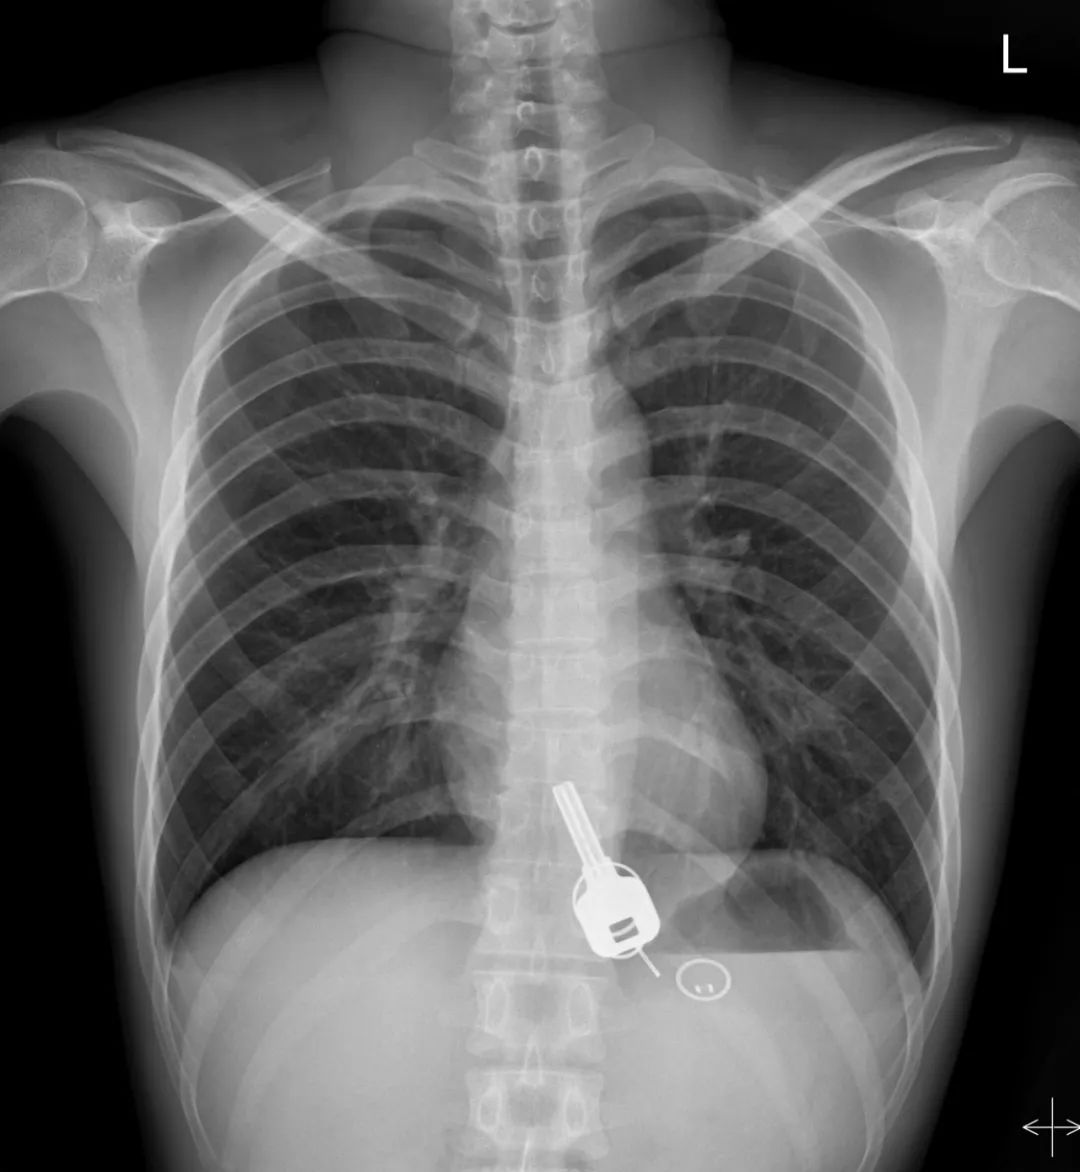

直到早上酒醒了,胸口很痛,忍不住来医院检查。结果,一拍X光,一把铁钥匙、2个钥匙扣、1个门禁牌清楚显示在肚子胃区的位置上。